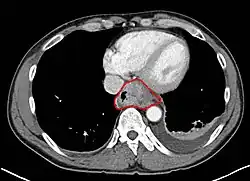

- Lower thoracic esophagus and EG junction:

- Inferior pulmonary veins to the stomach; includes the intraabdominal portion of the esophagus

- By endoscopy, 30 to 40 cm

- For cancers arising near the EGJ, they are staged as esophageal/EGJ if the epicenter is in the lower thoracic esophagus, the EGJ, or within the proximal 5 cm of the stomach (cardia) and extend into the EGJ or esophagus

- Those with an epicenter in the stomach greater than 5 cm distal the EGJ, or those within 5 cm of the EGJ but that do not extend into the EGJ or esophagus, are staged as gastric

- GE junction: (Classification by Siewert: PMID 11525305, PMID 9823902), center within 5 cm proximal/distal to GEJ

- Type I (distal esophagus) - arises from area with specialized intestinal metaplasia of the esophagus. Commonly, center of the tumor located 1 - 5 cm above the gastroesophageal junction

- Type II (cardia, considered gastric) - arises from the cardiac epithelium or short segments with intestinal metaplasia at the GEJ. Commonly, center of the tumor located 1 cm above to 2 cm distal to GEJ

- Type III (sub-cardia, considered gastric) - arises from subcardial location and infiltrates GEJ from below. Commonly, center of tumor >2 cm distal to GEJ